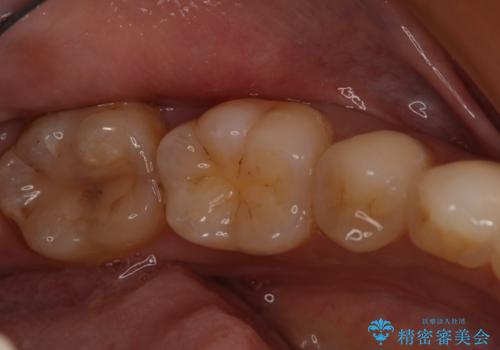

- 左下6、7番の虫歯をセラミックにて治療を希望された患者様です。

切削量を考慮してセラミックインレーを選択しました。

7番は虫歯が深かったのでCR裏層した上で形成、印象をしています。